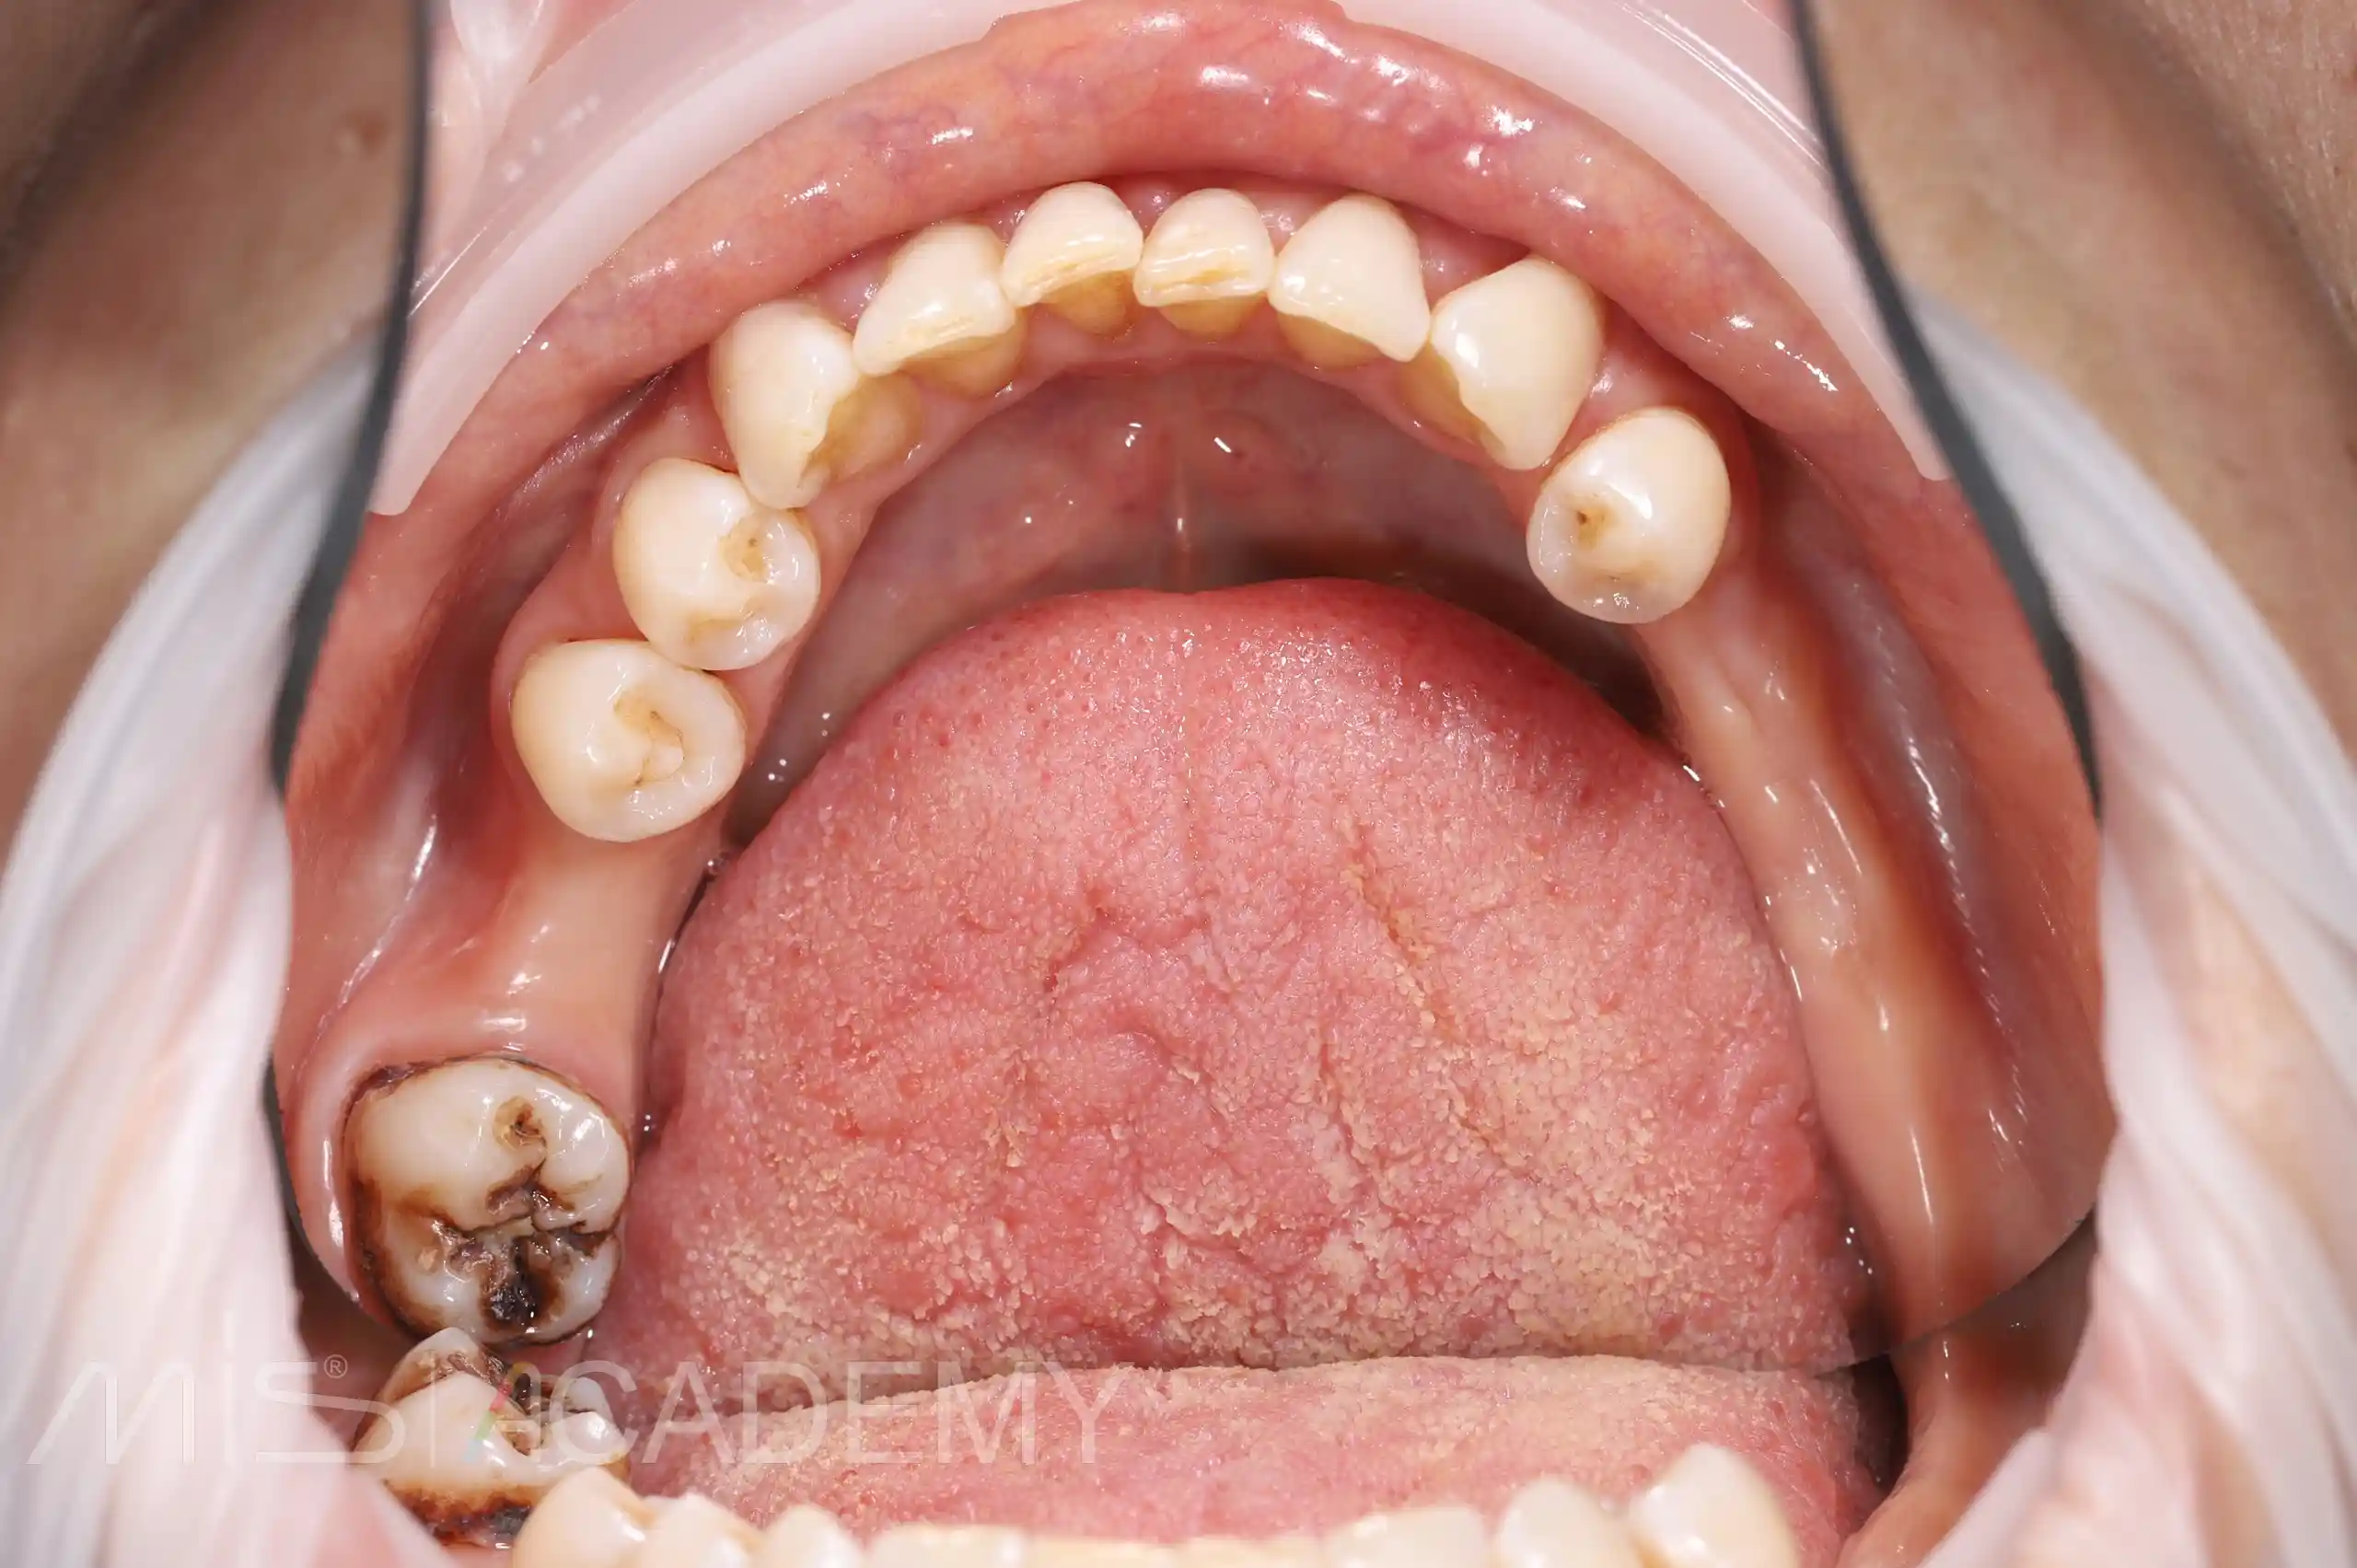

Установка имплантатов MIS C1 в области 46, 35, и 37 по навигации.

— ССТ, были добавлены методики Poncho.